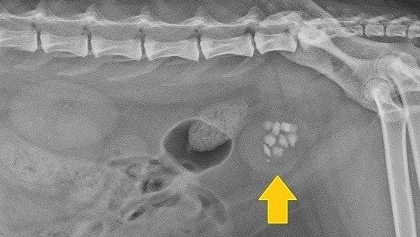

Мочекаменная болезнь у котов/кошек

Практически каждый день ко мне на прием приходят владельцы кошек и котов с жалобами на то, что их питомец не может пописать или делает это достаточно часто и даже ходит с кровью. Конечно самая распространенной причиной такого недуга является идиопатический цистит кошек, вот статья про него: Для начала необходимо поставить диагноз "Мочекаменная болезнь" (МКБ). Что же такое МКБ? МКБ это заболевание, которое сопровождается образованием в мочевыводящих путях (почки, мочеточники, мочевой пузырь) камней...